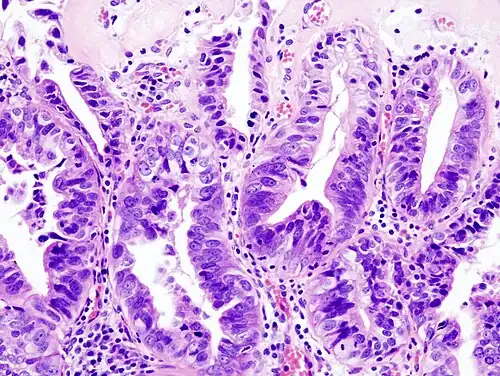

Gallbladder adenocarcinoma lymphatic invasion histopathology -

Gallbladder adenocarcinoma histopathology